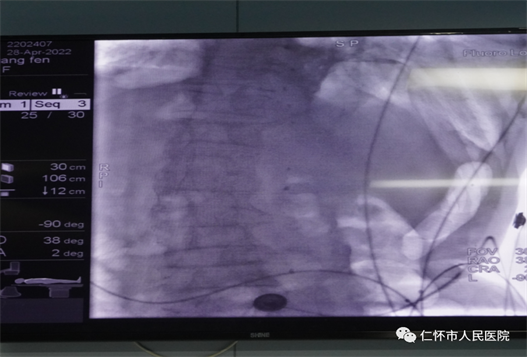

4月28日,仁怀市人民医院举行ERCP手术室启动仪式,并成功开展仁怀首例ERCP手术。院党委领导班子成员、相关科室负责人及肝胆甲乳外科医护人员参加启动仪式,仪式由副院长张岚主持。

仁怀市人民医院首例ERCP手术的成功实施,意味着肝胆甲乳外科微创手术的发展,再次上升一个台阶,标志“三镜联合”(腹腔镜、胆道镜、十二指肠镜)微创治疗胆胰疾病,已可实现。广大胆胰疾病患者,足不出县,即可享受三甲医院高超的医疗技术服务。

ERCP是在电子十二指肠镜下由口腔经十二指肠乳头插管注入造影剂,从而逆行显示胰胆管的造影技术,在 ERCP 的基础上,可以进行十二指肠乳头括约肌切开术(EST)、内镜下鼻胆管引流术(ENBD)、内镜下胆汁内引流术(ERBD )等介入治疗,是国际公认的胰胆管疾病诊断金标准,一般无需麻醉。